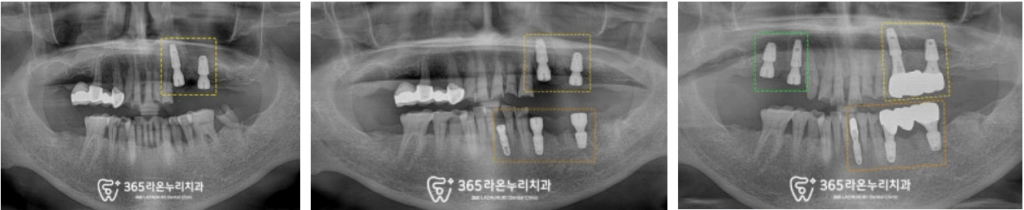

일부 순서는 조금 섞여있으나

수명을 다한 기존 이는 빼고

픽스처를 심은 모습입니다.

오른쪽은 저작힘이 약하시고

왼쪽은 식사가 힘드셨기에

빠르게 진행해 드리려 노력했습니다.

이렇게 순차적으로 보면

이해하시는데 훨씬 수월하실 겁니다.